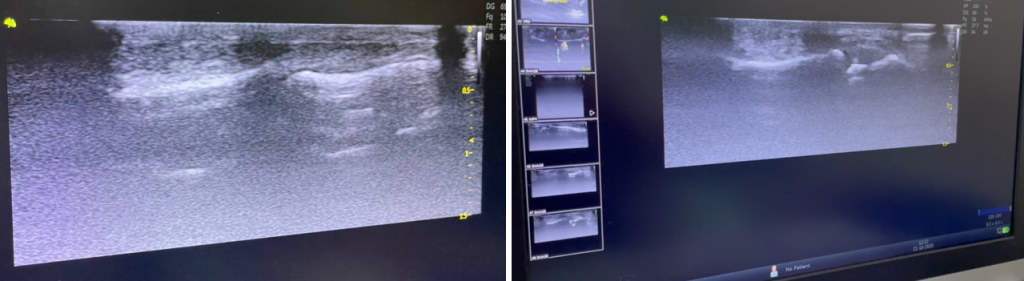

Наступний етап – ультразвукова діагностика.

УЗД з використанням високочастотних датчиків з частотою 14-15-16 МГц і більше дозволяє візуалізувати ділянку (кріплення) ентеза сухожилка до дистальної фаланги, та виявити ймовірний відрив кортикального фрагмента.

Проведення функціональних проб під час УЗД — візуалізує діастаз культі сухожилка (зміщення) від місця кріплення.

Пошкодження дистального ентеза сухожилка довгого розгинача 2 пальця. УЗД.